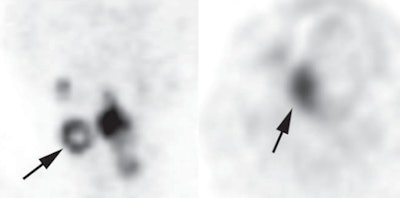

As good as these quantitative factors were, the shape of FDG uptake was better. Patients with sphere-shaped patterns of FDG uptake were almost 19 times more likely to survive than those with ring-shaped patterns (hazard ratio = 18.92).

Of the 108 patients, 14 had ring-shaped patterns and 94 had sphere-shaped patterns. Approximately 90% of those with sphere-shaped patterns survived for more than six years. In comparison, 10% of subjects with ring-shaped patterns survived for more than 36 months.

"Our findings suggest that the uptake pattern on FDG-PET/CT can provide better prognostic information than conventional quantitative patterns," the authors wrote. This could be because uptake patterns better reflect intratumoral necrosis or heterogeneous morphology, they added.